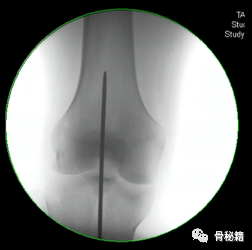

5、钉子的深度。逆行髓内钉的最佳深度是布鲁门萨线的顶点位置,正位居中

近端一般是小粗隆水平以上

6最后提一点锁钉的小技巧,不要造成主任打主钉5分钟,我们锁钉2小时。我们透视的时候,要把锁定空透成两个圆形,但是在操作中往往是椭圆形,这个时候根据椭圆形的长轴来方向来移动C臂,就可以透一个好的圆形了,在此情况下完成锁钉就相对容易些。